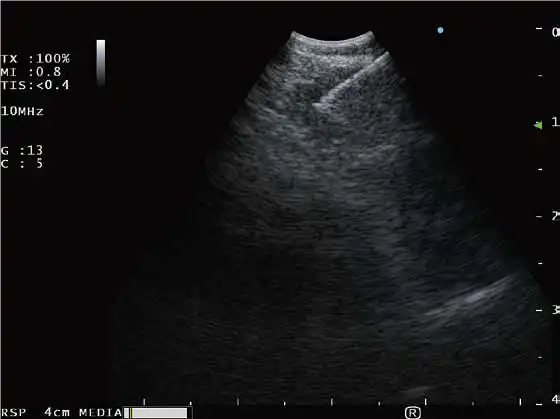

与凸阵扫描超声支气管镜配套使用

B-模式 H-FLOW模式 ELST模式